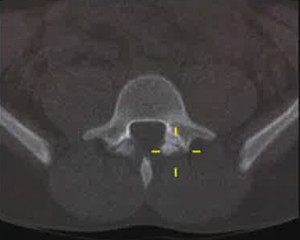

TAC-espondilolisisTAC-espondilolisisGimnastas, practicantes de fútbol americano, levantadores de pesas, luchadores, bailarines y conductores son las personas más comúnmente afectadas. Por ello, en estos casos debe considerarse la posibilidad de una fractura por sobrecarga de la pars interarticular que puede dar lugar a una espondilolisis y/o espondilolistesis.

La gran mayoría de los defectos espondilóticos ocurren en el nivel L5 (85 – 95%), siendo L4 el segundo nivel más comúnmente involucrado (5-15%), mientras que las zonas lumbares superiores rara vez se ven afectadas. Este defecto se ve con relativa frecuencia en los estudios radiográficos con vistas posteroanterior y lateral, aunque las vistas dinámicas y oblicuas parecen determinar la estabilidad vertebral y conducir al diagnóstico.

Desafortunadamente, se realizan diagnósticos erróneos de espondilólisis. Un factor de complicación en las primeras etapas de la enfermedad que conduce a un diagnóstico erróneo es el hecho de que las radiografías simples, incluso las oblicuas, pueden no ser útiles en la etapa de fractura por sobrecarga. Otras técnicas de imagen, como la gammagrafía ósea, posiblemente, la resonancia magnética o Tomografía computarizada de emisión monofotónica (SPECT) deben ser utilizadas al inicio del proceso de diagnóstico. En el ámbito de la atención primaria, el diagnóstico precoz de elemento de participación posterior relacionado con el dolor lumbar, ya sea en la etapa de la fractura por sobrecarga del pars o por espondilolisis temprana, puede prevenir la progresión de la enfermedad y evitar la necesidad de una intervención quirúrgica.